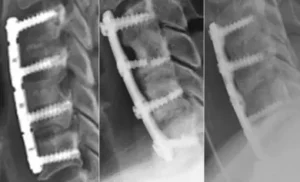

A spinal fusion is usually a permanent injury since the herniated disc must be removed and replaced with an artificial implant followed by hardware to fuse the two adjoining vertebrae. This results in a prolonged recovery and permanent limitation of motion, nerve damage, possible side effects, need for revision surgeries, and lifelong pain and suffering.

A spinal fusion is often medically recommended if the range of motion in the spine is severely decreased or if a vertebrae is fractured such as a burst fracture or a compression fracture. Other reasons a doctor may recommend spinal fusion surgery is to repair a herniated disc that leads to cauda equina syndrome, spinal stenosis, spondylosis, lordosis, spondylolisthesis, scoliosis or other degenerative changes that have become unbearable for the patient. A spinal fusion can also be a follow up or revision surgery for a failed back surgery.

Intervertebral Implant

Surgery is From the Front

A corpectomy or vertebrectomy is a surgical procedure that involves removing all or part of the vertebral body (Latin: corpus vertebrae, hence the name corpectomy), usually as a way to decompress the spinal cord and nerves. Corpectomy is often performed in association with some form of discectomy.